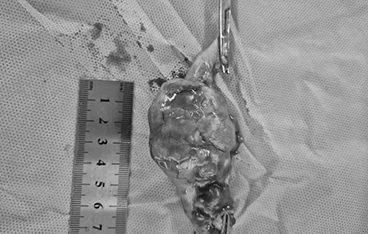

담낭점액종

담낭절제술 + 담관 Flushing

• 담낭절제술